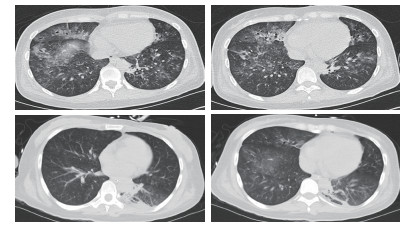

1 资料与方法 患者女性,29岁,以“恶心、呕吐1个月余,进食困难伴饮水呛咳半月,呼吸困难5 d,发热1 d”主诉收入北京世纪坛医院。患者病史长且复杂,笔者根据其先后就诊医院对其病史进行总结(表 1)。2018年5月10日患者在北京西客站候车过程中出现呼吸困难加重,随后出现呼之不应,立即送至本院急诊。至本院急诊抢救室时,患者生命体征心律166次/min,呼吸32次/min,血压80/47 mmHg(1 mmHg=0.133 kPa),氧饱和度80%,体温39.5℃,查体:浅昏迷,双瞳孔等大正圆,直径约2 mm,对光反射存在,无颈项强直,口周及口腔内可见较多清亮唾液,双肺呼吸音粗,双肺可闻及少量湿性啰音,左下肺为著,心律齐,各瓣膜听诊区未及杂音。腹部查体未见异常。双侧腱反射存在,双侧病理征阴性。血气:pH 6.95, PCO2 88 mmHg, PO2 48 mmHg, Lac 8.0 mmol/L, 故立即予气管插管、呼吸机辅助通气, 建立静脉通路补液及去甲肾上腺素泵入升压治疗,并立即收入本院急诊ICU。患者入院后主要血化验结果见表 2。心脏彩超提示弥漫性室壁运动异常,EF为45%,考虑感染相关心肌抑制。胸部CT提示双肺弥漫大小不等点片、斑片状高密度影,其内可见支气管走行,纵隔内可见多个大小不等淋巴结影,考虑双肺感染(图 1)。下肢血管超声、头颅CT、腹部CT均未见明显异常。患者入院后继续予气管插管接呼吸机辅助通气,呼吸机模式PC,起始参数:P 18 cmH2O(1 cmH2O=0.098 kPa),f 14次/min,PEEP 4 cmH2O,FiO2 40%;去甲肾上腺素静脉泵入及静脉补液升压治疗;肠内营养治疗;结合患者胸部CT及其他化验结果,诊断首先考虑重症肺炎,脓毒症,脓毒性休克,Ⅱ型呼吸衰竭,因此抗感染采用联合抗细菌、真菌及病毒全覆盖方案,同时予静脉输注人免疫球蛋白(IVIg)20 g/d ×5 d,静脉输注甲泼尼龙80 mg/12 h×4 d→40 mg/12 h×7 d→40 mg/d×3 d→甲泼尼龙片20 mg/d口服。经过上述治疗,患者体温逐渐下降至正常,神志逐渐转清,四肢肌力逐渐恢复至正常,呼吸机条件逐渐下调至模式PS,参数P 8 cmH2O,FiO2 40%,循环逐渐稳定并停用血管活性药物。复查主要血化验结果(表 3)均较前好转。抗感染治疗后前后2次复查胸部CT均提示肺炎较前吸收好转(图 2)。此时患者能脱机,但却不能拔管,且患者无咳嗽反射亦不能遵嘱吞咽。